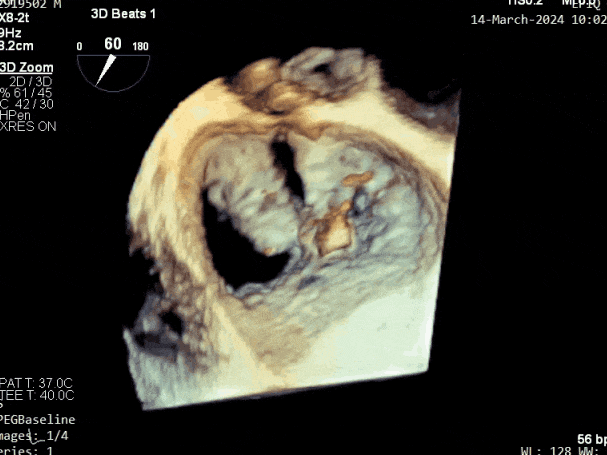

第三个瓣膜夹释放后评估,释放后评估,二尖瓣呈双孔,组织桥张力合适,瓣膜夹轴向与二尖瓣闭合线垂直,无残余反流

肺静脉血流频谱恢复为收缩期正向

2. 本例患者外院超声心动图考虑二尖瓣前叶脱垂,入院后经食道超声心动图明确该患者为二尖瓣后叶活动受限,呈房源性栓系,二尖瓣前叶假性脱垂,超声特征表现为心房功能性二尖瓣反流终末期,呈现出很典型的二尖瓣后瓣环向左室游离壁顶部位移和后叶挛缩表现,同时合并有明显的二尖瓣瓣环扩张、圆形化,左房增大等不利因素,术中通过精准的影像指导和手术操作,成功行TEER,二尖瓣反流程度减轻至微量。